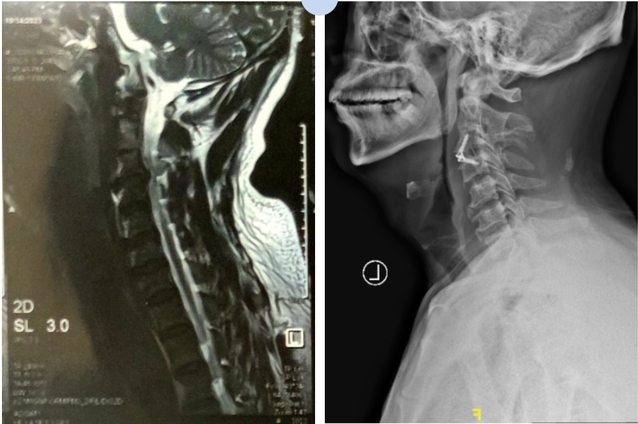

●一位患者被颈椎病困扰多年,颈椎长期不稳定且合并椎间盘突出,椎体后缘增生,韧带骨化,导致突出物的硬度很高,就像一块“石头”压迫脊髓,再不处理,将造成更加严重的后果。

●另一位患者因发生车祸,颈椎甩了一下,之前本就突出的椎间盘加重,压迫脊髓,造成瘫痪!

术后患者椎间隙高度恢复,生理曲度恢复,神经受压解除;头部胀痛,右上肢放射痛得到缓解。

巨大的突出物已切除,椎间隙高度恢复,椎管容积扩大,神经压迫解除,双手麻木感消失。